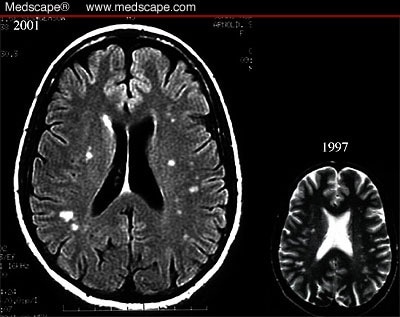

Case 14: Headache and Unilateral Visual Changes

Previous migraine studies found atrophy of cortical regions in the brain related to pain processing. These spots in the migraine brain look virtually identical to the spots we see in other conditions like people with migraine and celiac disease both have the same type of spots on their brain mri. A migraine can cause severe throbbing pain or a pulsing sensation, usually on one side of the head.

Chronic migraine can be debilitating for those who experience it. Migraines may be triggered by lack of sleep, changes in the weather, hunger, excessive stimulation of the senses, stress, or other factors. For most, chronic migraine is a lifelong condition—one that follows patients throughout their years probably the question on every patient's mind is whether or not chronic migraine can cause various studies have confirmed the presence of deep white matter lesions or abnormalities in the brain. The headache typically is accompanied by nausea.